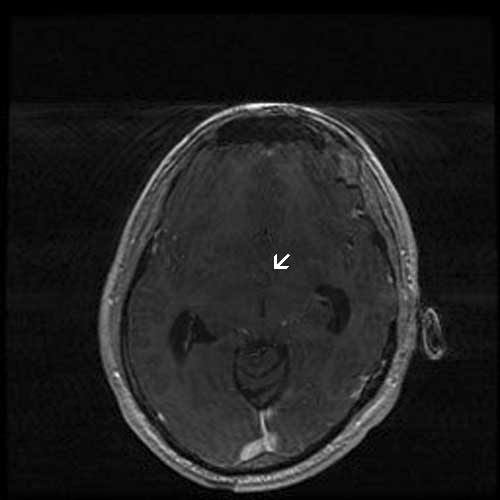

History: The patient was a 53 year-old man who presented with a 3 week old history of headache associated with walking and vision changes. Imaging studies demonstrated prominent dilation of lateral ventricles and a cyst in the third ventricle. On MRI scan, the cyst is 13 x 9 x 9 mm and is located at the roof of the third ventricle. It has an enhancing mural nodule. The cyst was removed and generated the specimen here.

MRI T1-Contrast